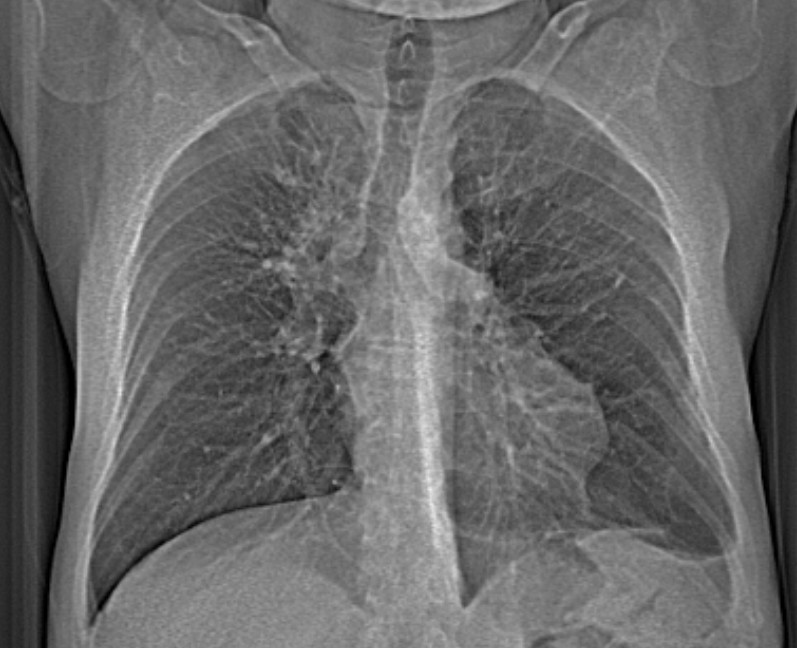

- გულმკერდის CXR 2 თვით ადრე.